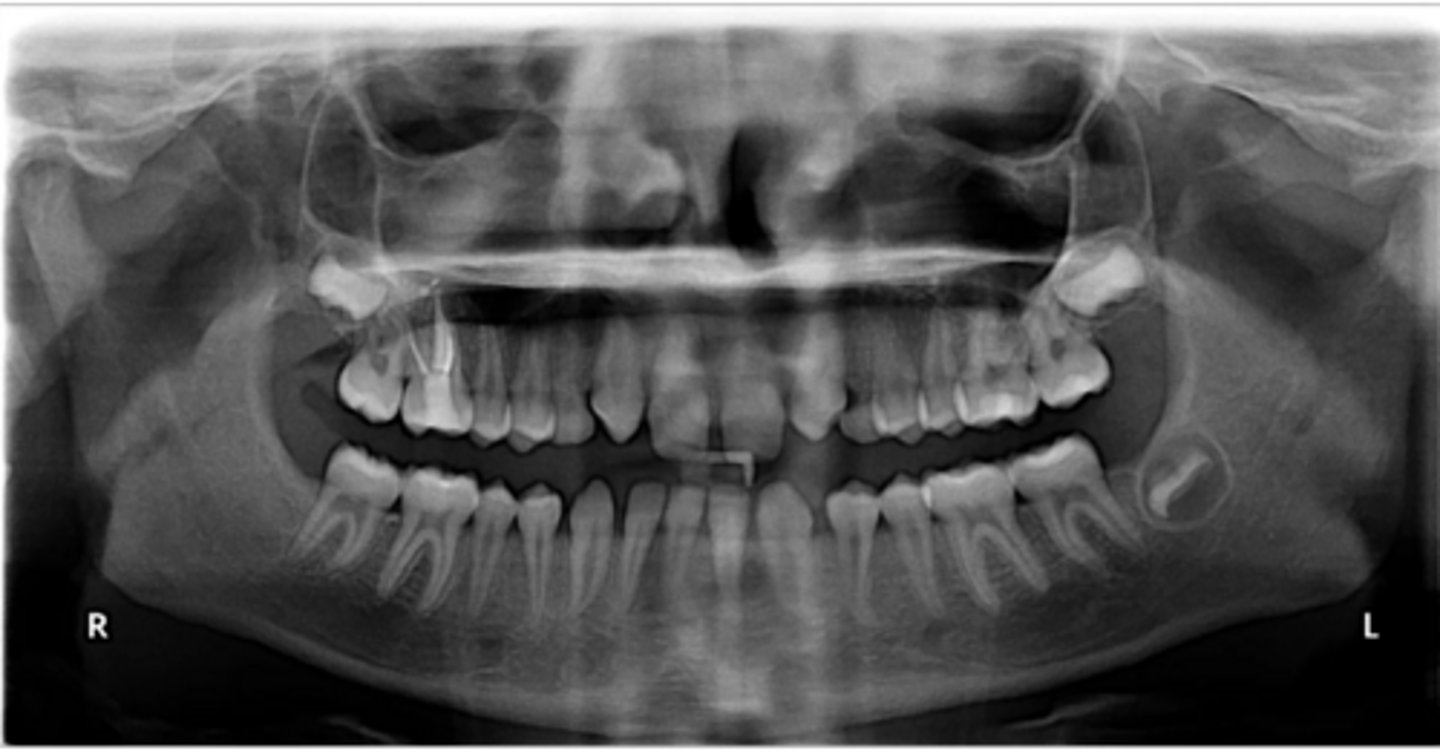

No

Are there congenitally missing teeth in the maxillary arch?

Are there congentially missing teeth in the mandibular arch?

Any supernumerary teeth?

Yes - mandibular second molars

Any impacted teeth?

Yes

Are the condyles symmetrical?

Maybe in the upper molars

Are there any dilacerated roots?

Are there congenitally missing teeth in the mandibular arch?

Are there any supernumerary teeth?

Are there retained primary teeth?

A little bit

Is there crowding?

Is there any pathology?

Possibly #20